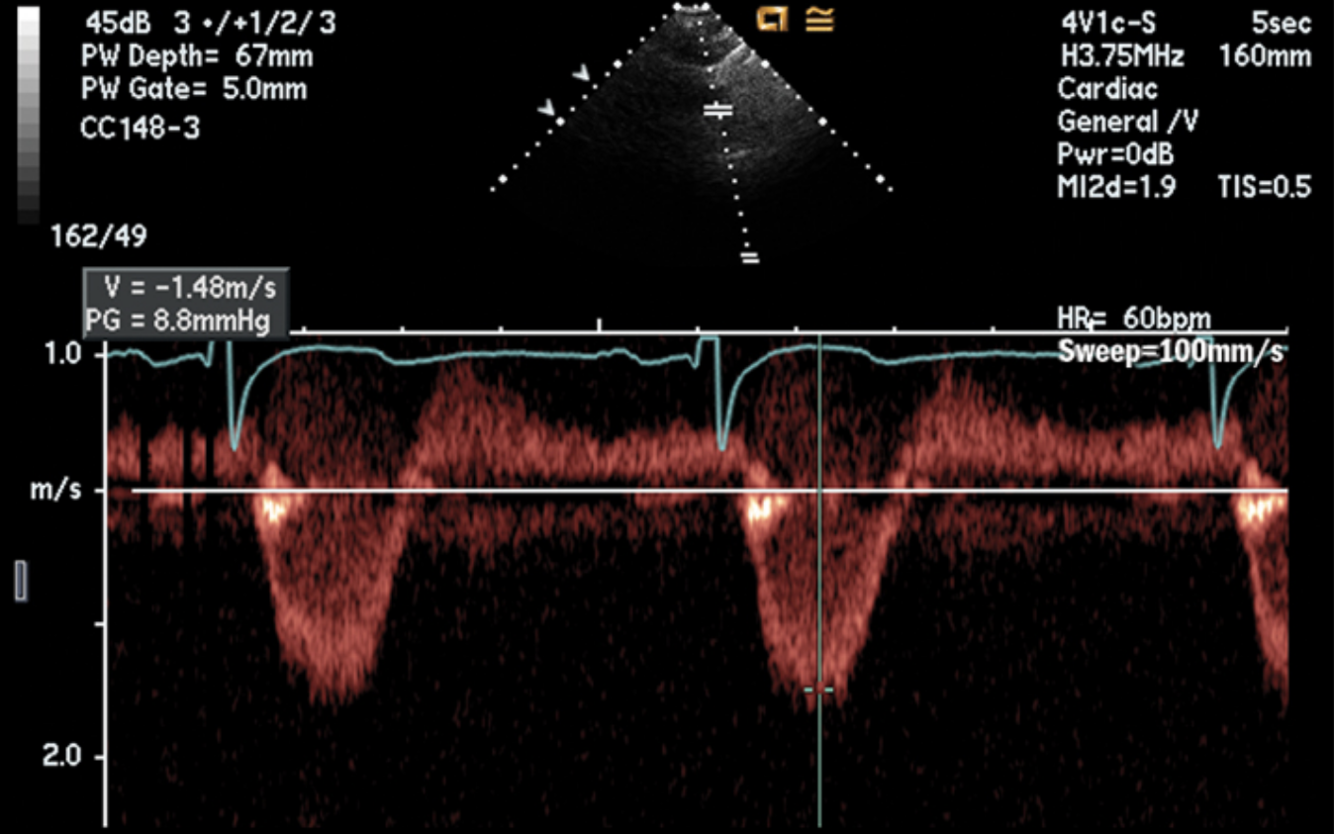

**Obtained using CW doppler